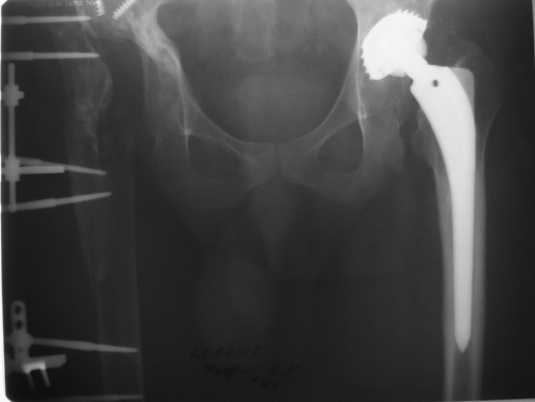

2005 г. при падении с высоты - перелом бедра в верхней трети, наложение АВФ . 3 года пациент ходил с аппаратом(рис. 3).

Обращение в нашу клинику в 2008 г. - демонтаж аппарата (рис. 4). Сегодня укорочение 8 см. Слева - протез стабилен, безболезнен.